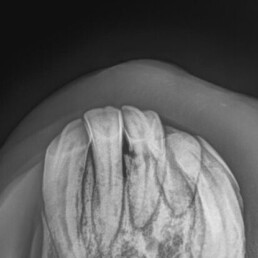

Der 22-jährige Wallach „Fjalvard“ (Name geändert) hatte vorberichtlich seit längerer Zeit hgr. Schmerzhaftigkeit und Probleme beim Fressen. Er hatte Fisteln mit eitrigen Ausfluss an drei Schneidezähnen, von denen einer bereits gebrochen war. An den Schneidezähnen war sein Zahnfleisch gerötet und rückgängig.

- sichtbare Zahnveränderungen: Fisteln/Rötungen/Lockerung/Rückgang/Zahnfleisch o.ä.